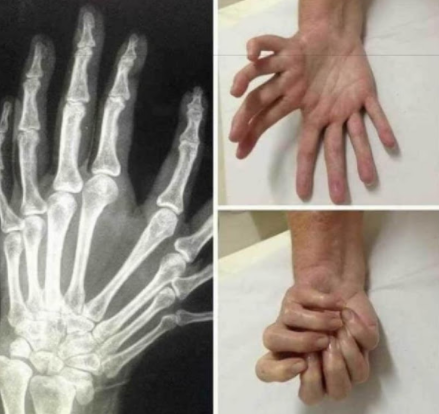

②鏡に映し出されたような手

この症状は研究の材料になりそうですよね。

ただ、最も興味深いのは、全世界でも医学的な根拠や事例が100もないということ。